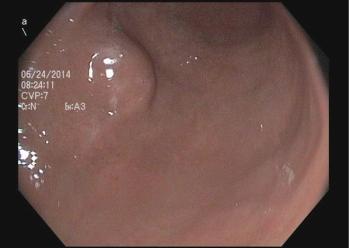

These endoscopic findings help explain worsening dysphagia in a 32-year-old man. Esophageal biopsies prove positive for eosinophilia. How would you proceed?